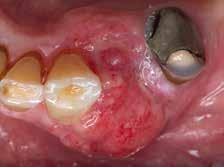

Im Zuge implantatprothetischer Rehabilitationen wird bei Vorlie gen einer reduzierten bukko-oralen Alveolarkammbreite bzw. auch der (in geringem Maße) -höhe eine vorangehen de knöcherne, latero-vertikale Augmen tation durchgeführt, um eine erfolgreiche ossäre Verankerung des Implantats wie auch ein ansprechendes ästhetisches Ergebnis nach abgeschlossener prothe tischer Versorgung anzustreben (siehe Abb. 1–8). Hierfür stehen verschiedene augmentative Operationstechniken zur Verfügung, wobei die autologe Blockaugmentation bislang am häufigsten angewandt wird. Obwohl autologe Knochenblöcke nach wie vor als „Gold standard“ gelten, kommen allogene, personalisierte, CAD/CAM-gefräste Knochenblöcke aufgrund ihrer hohen Passgenauigkeit vermehrt bei 3D-kom plexen Knochendefekten zum Einsatz. Gewonnen werden allogene Knochen blöcke vor allem aus Femurköpfen (nach sorgfältigster Spender:innen-Auswahl und Aufbereitung) von Patient:innen, welche eine Hüft-Endoprothese benö tigen. Diese Blöcke werden mithilfe des zuvor durchgeführten DVTs/CTs dem Defekt kongruent (3D-CAD) digital geplant und anschließend maschinell (3D-CAM) gefräst. Im Zuge des Eingriffs entfällt so der Vorgang der Blockentnah me, was wiederum zu einer deutlichen Verkürzung der OP-Dauer führt und in einer ausgeprägten Verminderung post operativer Beschwerden und möglicher Komplikationsquellen resultiert. Da der allogene Block dem Empfängerbett bereits (je nach Bildqualität) optimal angepasst ist, entfällt im Vergleich zur

Abb. 1: Intraoperative Ansicht des komplexen Defektes 21 nach Entfernung eines Wurzelspit zen-resezierten Zahnes nach Monaten

Abb. 3: Fixierung des kongruenten, allogenen Knochenblocks mit einer Osteosynthese schraube stabilisiert

autologen Blockaugmentation meist eine zeitintensive Adaptierung des Augmenta tes an das Empfängerbett. Postoperativ konnte im Rahmen lateraler Augmentationen mittels allogener Kno chenblocktransplantate allerdings eine deutlich höhere Rate an Wundheilungs störungen/Komplikationen – vor allem Schleimhautdehiszenzen – beobachtet

Abb. 4a–4b: „Biologisierung“ einer Kollagen membran mit der flüssigen Phase des PRFs (a), auf den Block aufgelagert (a) und die viskösprämembranöse Phase (b) des PRFs nach Abtrennen des überschüssigen Blutkoagulums vor dem Pressvorgang

werden. Für ein komplikationsloses Einheilen des Knochenblocks ist eine suffiziente Wundheilung des umgeben den Weichgewebes notwendig.

Ziel der laufenden klinischen Obser vanzuntersuchung ist eine Optimierung durch Verwendung des aus Eigenblut gewonnenen „Platelet-Rich Fibrin“ (PRF). Dabei werden der Patientin oder

Patient:innen-individualisierter Knochenblock (allogen)

Abb. 5: Zwei PRF-Membranen über die Kolla genmembran (Block unterhalb) gelegt

dem Patienten vor dem Eingriff 100 bis 200 ml Blut in zwei verschiedenen Ampullen abgenommen. Diese werden während des Eingriffs wenige Minuten lang nach dem Protokoll von Chakroun (LIT!) zentrifugiert, wodurch eine flüssige und eine viskös-prämembranöse Phase des PRFs, abhängig von der verwendeten Ampulle, gewonnen werden kann. Die flüssige Phase wird dabei sowohl zur Rehydrierung und Bioaktivierung des ge friergetrockneten Spender:innen-Blocks als auch zur Benetzung der verwendeten Kollagenmembran benutzt. Pro Ampulle kann aus der gallertigen Phase binnen weniger Minuten eine ca. 1 x 2 cm große Membran gepresst werden. Diese wird zwischen Kollagenmembran und Weichgewebe eingebracht. Der Einsatz dieser beiden Phasen des PRFs kann

Abb. 6: Nach sechs Monaten abgeheilter Situs der augmentierten Region bei Implantation

Abb. 7: Inseriertes Implantat mit sowohl bukkal als auch palatinal suffizientem Knochenangebot

Abb. 8a: Kontrolle nach Implantat-Insertion

eventuell zu einer schnelleren Einhei lung des allogenen Blocks führen, vor allem steht allerdings ein eventueller positiver Effekt auf die Weichgewebs heilung des OP-Gebiets zur eventuellen Reduktion der Wundheilungsstörungen im Vordergrund. Dieser Effekt wird ak

tuell in der vorgestellten Untersuchung an der Abteilung für orale Chirurgie der Universitätszahnklinik Wien evaluiert, Patient:innen können bei Interesse (noch) eingeschlossen werden.•